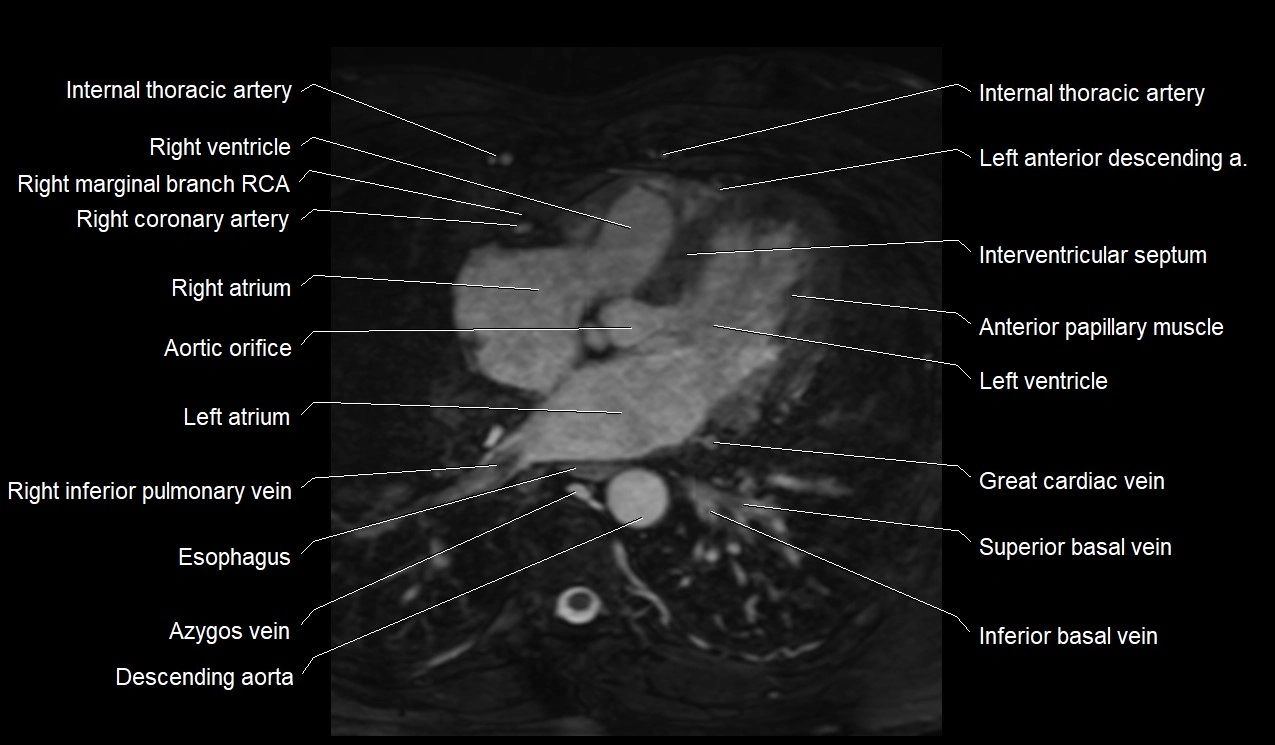

MRI image